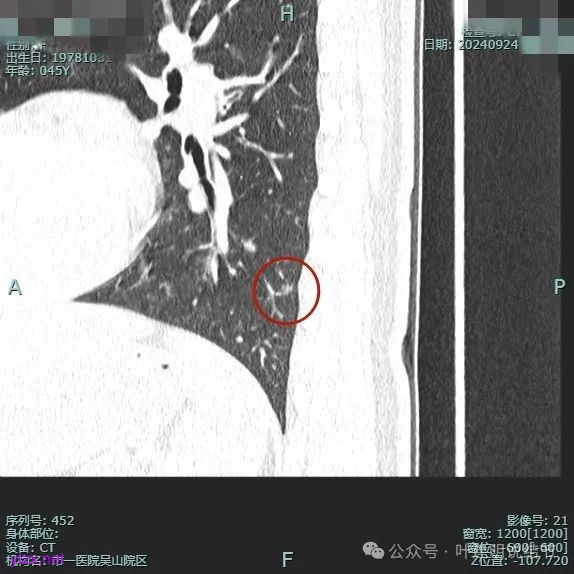

病灶2:

右中叶内侧段可见混合密度结节,大部分实性,形态与下叶背段的类似。

病灶1:

病灶是混合密度,边缘少许淡磨玻璃,灶内不太致密,表面不平,血管征有,但说不上明显异常增粗。

病灶紧贴叶间裂,而且感觉跨过肺叶,部分影响到上叶了,病灶本身密度虽实性为主,但是不太致密,有点松散的感觉。

总体实性部分密度较高,而磨玻璃部分密度较低,且瘤肺边界欠清,关键是跨叶间裂生长,这与肿瘤似乎不容易解释些。

毛刺有但不太锐利,磨玻璃有但偏淡,实性为但不太致密,叶间裂与之关系密切,病灶跨叶生长。

上图显得与肿瘤较为符合,但跨叶生长的话,侵袭力应该较强,可她这病灶较刚发现时进展并不太明显。

上图层面也较符合恶性,血管进入明显,有浅分叶的样子,整体觉得有一定收缩力与膨胀感。

病灶表面不平,混合密度,磨玻璃成分较淡。